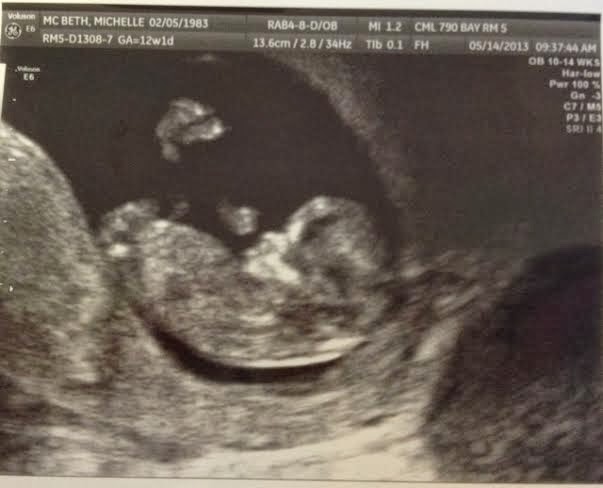

Ultrasound pictures from 12-week period.

Ultrasound pictures 12-weeks on left, 24 weeks on the right side.